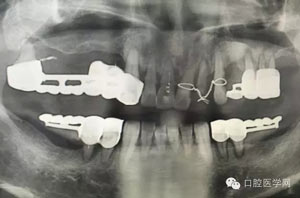

做根管的,都想做些難度大一點的,彎曲根管了、斷針了,可是臨床上很多時候是中等及以下難度的居多,我們要做的是盡我們所能做好這一部分,將我們力所能及的做好,而不是不切實際的幻想做一些我們條件設(shè)備不夠的病例。有些時候看到一些病例,很難想象是我們同行做的,我們是人,而不是神,我們也需要生活,我們追求效益沒有錯,我們給患者推薦好的材料,最終受益多的還是患者,這沒有錯,但是我們不是賣產(chǎn)品的,我們的本質(zhì)是醫(yī)療,不是流水線上的工人,將商品加工賣出去,我們所做的一切都是建立在符合修復(fù)設(shè)計原則的基礎(chǔ)上的,如若不符合,我們做的再美觀,再便宜,那又有什么意義呢?無論我們做什么樣子的修復(fù)體或者是治療,我們的標(biāo)準(zhǔn)是一致的,教科書上有明確的規(guī)定,我們這社會也有畸形,就拿簡單的冠修復(fù)來說,我們花費的精力是差不多的,我們需要的步驟是一樣的,但是價格差別那么大,是我們自己制定價格的問題,還是社會的問題?如若我們的冠的價格的制定差別不大,我們將更多的心思放到醫(yī)療本身上面,那么最終受益的還是患者,可是現(xiàn)在是顛倒的,我們成了產(chǎn)品的推銷者,整天想著怎么樣將價格高的冠賣給患者,而忽略了提高學(xué)習(xí)我們自身專業(yè)能力,我們整天想著怎么樣將環(huán)境打造的多么的好,然而材料上面卻是怎么樣的省怎么來,什么便宜用什么,裝修上面我們可以花很多,材料我們卻很摳,有時候我們材料買很好,可是我們卻束之高閣,很多時候我們講理念,講概念,可是我們卻很少腳踏實地的去做我們的專業(yè),只是用這些新鮮的名詞去和患者溝通。給大家看幾張不良的修復(fù)設(shè)計。